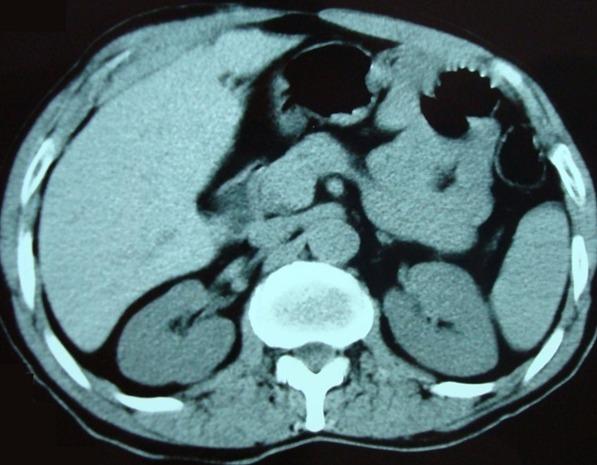

Gallbladder agenesis is a rare congenital anomaly. This study aimed to highlight the epidemiological aspects of this condition as well as the peculiarities of its diagnostic and therapeutic management through three case reports. Two adults were admitted to Hospital with hepatic colics and dyspepsia. Ultrasound showed multilithiasic scleroatrophic vesicle. In one of the two patients, CT scan results showed a stone at the level of scleroatrophic vesicle. These two patients were wrongly operated for vesicular lithiasis by using conventional method. The absence of gallbladder was detected during surgery. In order to confirm post-operative diagnosis, the first patient underwent biliary MRI. The other patient was lost to follow-up. The third patient was a 13-year old child hospitalized with acute pancreatitis. Vesicular agenesis was suspected based on its scannographic aspect and then confirmed using biliary MRI. This patient didn't underwent surgery.

胆囊缺如是一种罕见的先天性异常。本研究旨在通过三例病例报告强调该病症的流行病学方面及其诊断和治疗管理的特点。两名成年人因肝绞痛和消化不良入院。超声显示为多发结石性硬化萎缩性胆囊。在这两名患者中的一名,CT扫描结果显示硬化萎缩性胆囊处有结石。这两名患者通过传统方法被误诊为胆囊结石并接受了手术。手术中发现胆囊缺失。为了确诊术后诊断,第一名患者接受了胆道MRI检查。另一名患者失访。第三名患者是一名13岁儿童,因急性胰腺炎住院。根据扫描图像怀疑胆囊缺如,随后通过胆道MRI得以确诊。该患者未接受手术。